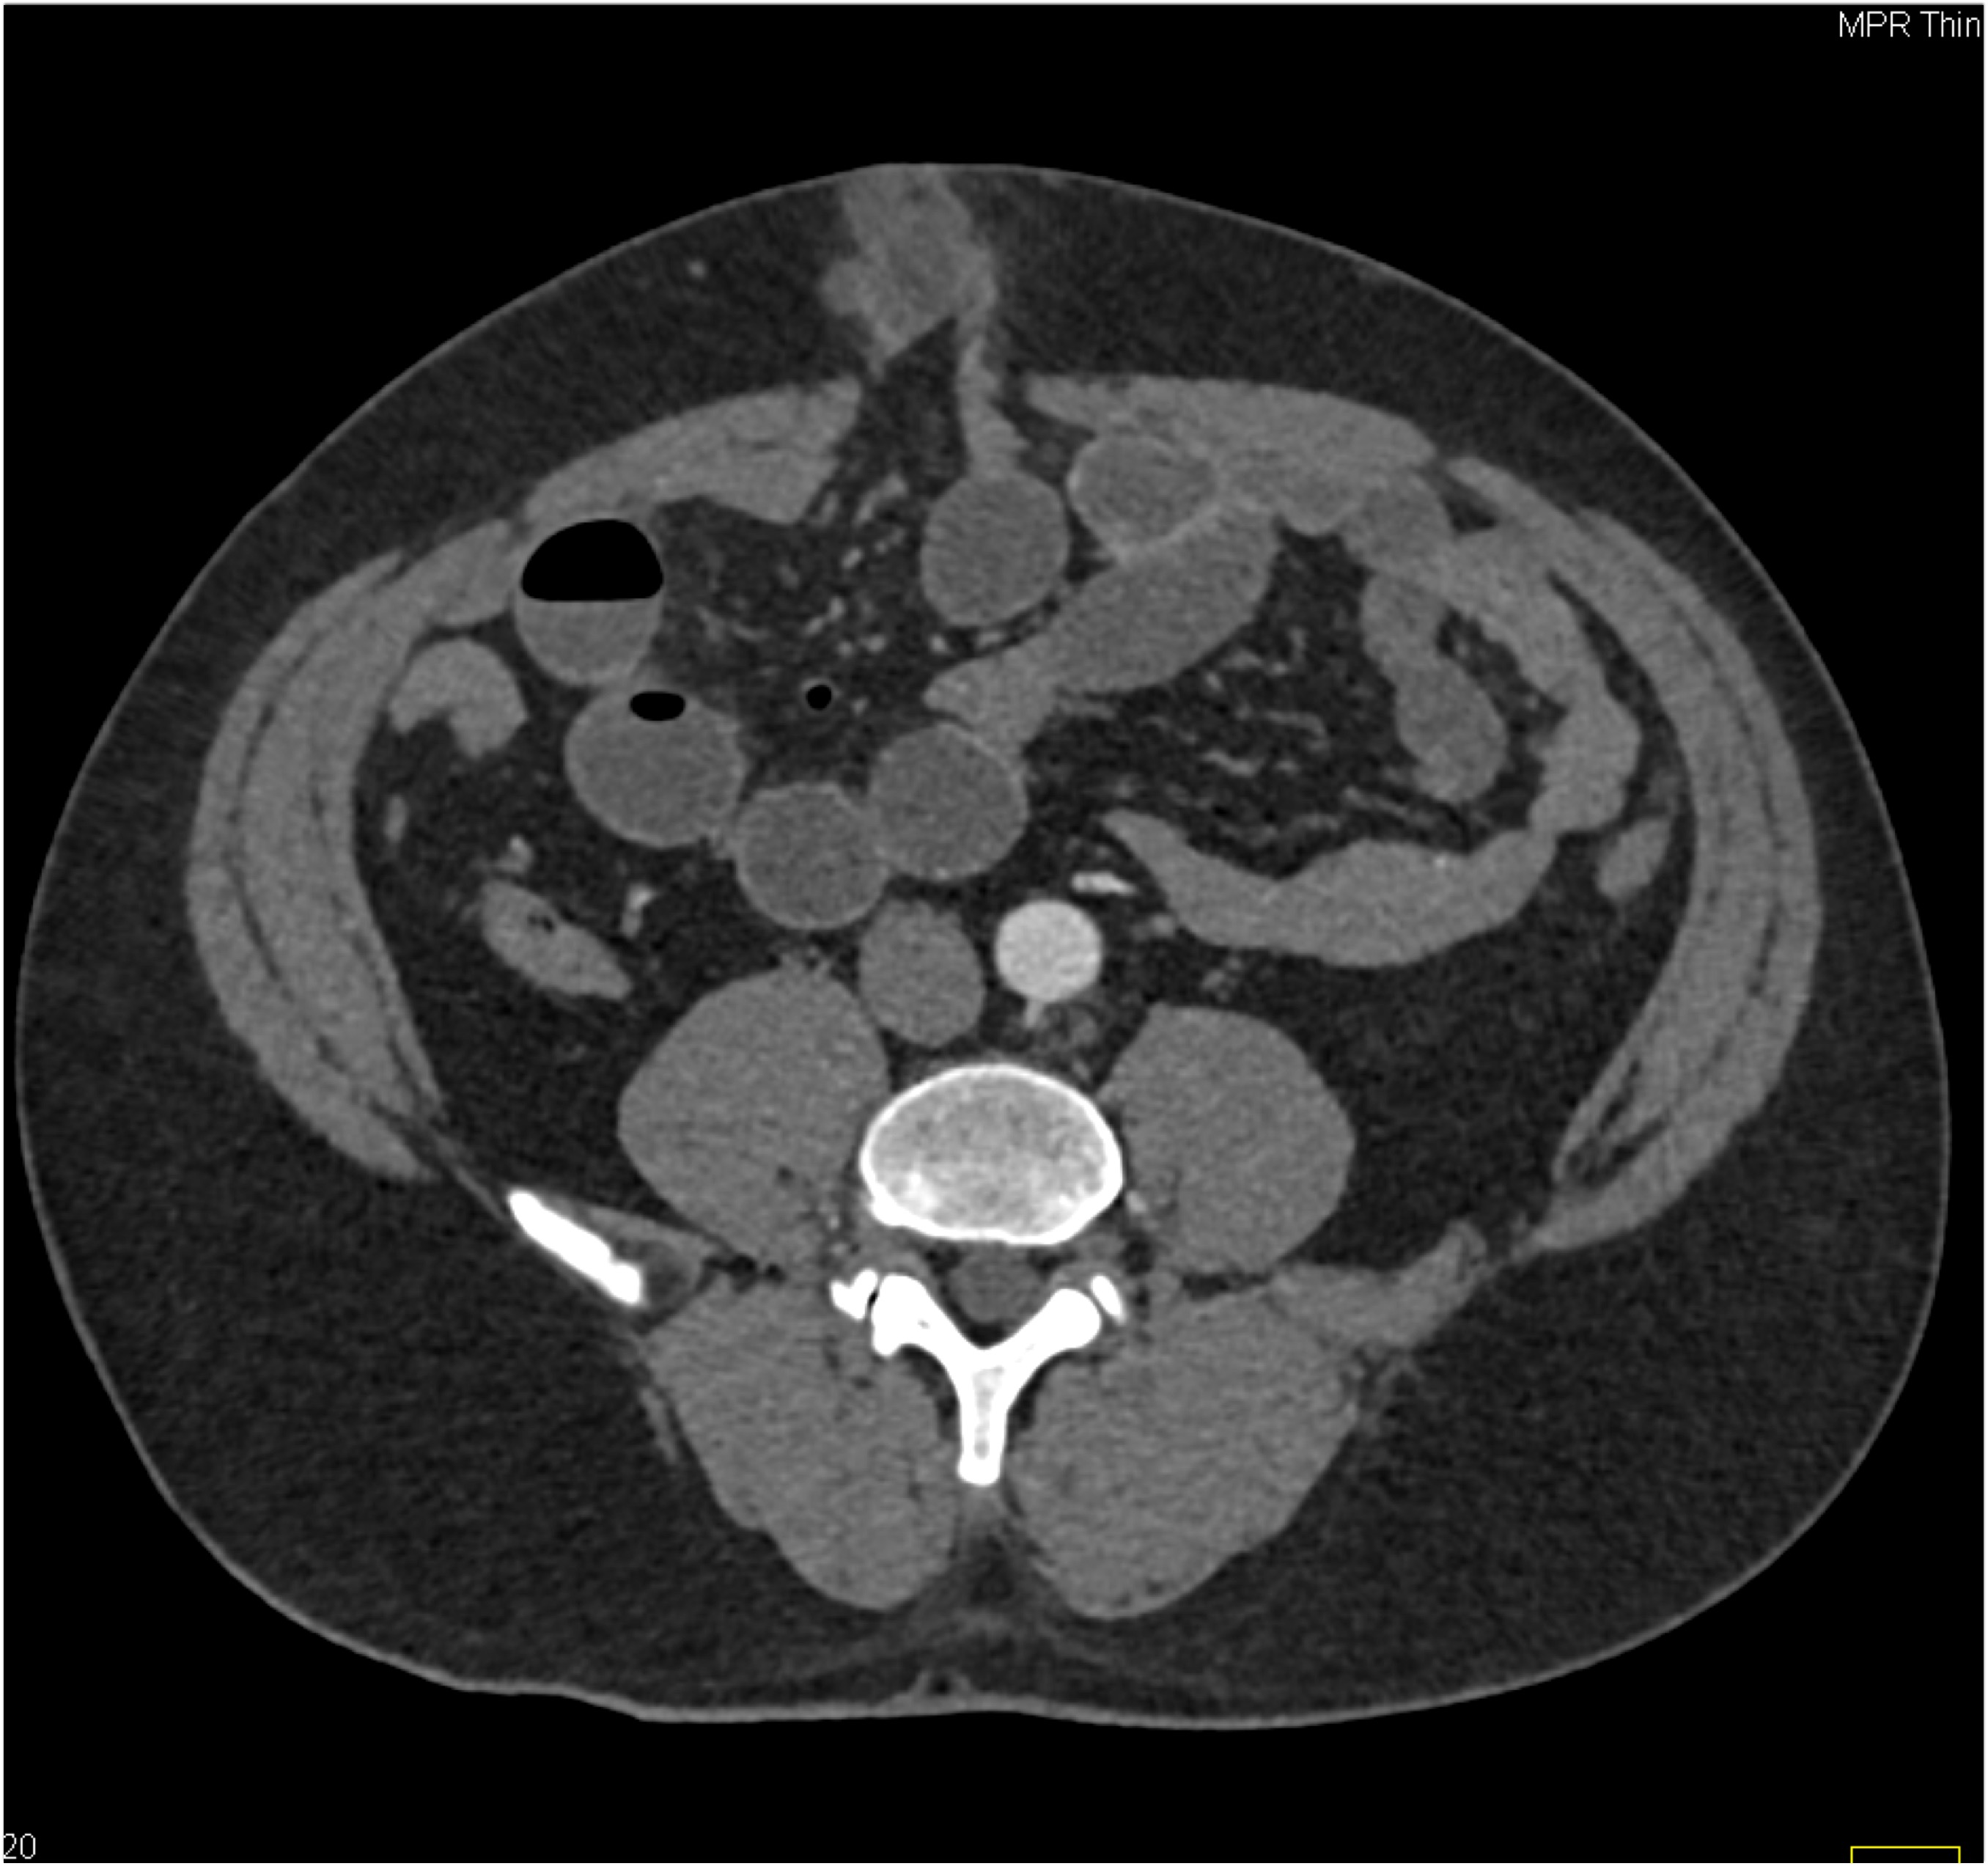

5) The most likely diagnosis in this case is?

femur fracture

GSW with active bleed from SFA

GSW without source of bleed

GSW with vessel spasm in SFA